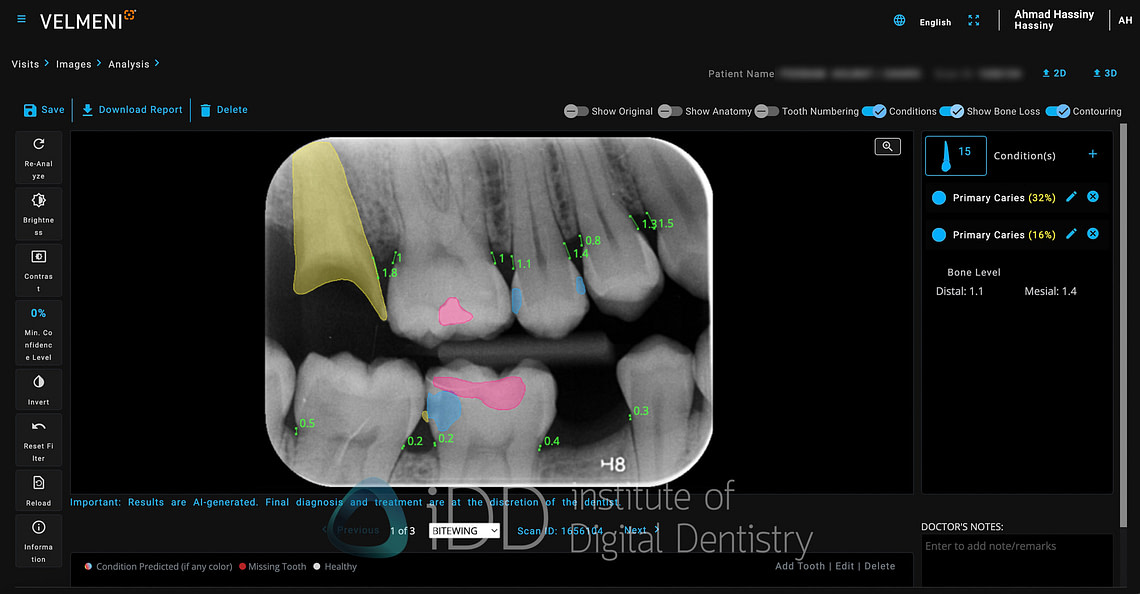

When you click on any tooth, the window on the right provides additional details about the finding, including measurement data and confidence levels. The ability to edit or dismiss AI findings is straightforward, acknowledging that professional judgment should always take precedence over automated detections.

One of Second Dentist's useful features is its ability to toggle between different visualization styles for AI findings. The platform offers two display modes: contour shading and box indicators. The contour shading option, which I find far more effective, fills in detected areas with semi-transparent colors that follow the natural contours of the findings. This creates a cleaner, more intuitive visualization that makes it easier to understand the extent and shape of detected pathologies.

Second Dentist takes a straightforward approach to caries detection with a simple marking system. The platform uses a single color - blue - to highlight areas of suspected decay, whether it's primary caries in untreated teeth or secondary caries around existing restorations. The blue markers clearly stand out against the grayscale of the radiograph, drawing attention to suspicious areas that warrant closer examination.

In daily practice, I've found this visualization particularly effective for patient communication. The blue highlights make it easy to explain findings to patients. Whether pointing out early decay between teeth or showing secondary caries beneath an existing restoration, the consistent blue marking system helps maintain clear communication.

While other AI platforms use multiple colors or the severity of the decay, Second Dentist's single-color approach doesn't seem to have this feature yet.